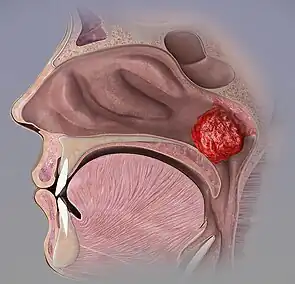

Enlargement

An enlarged adenoid, or adenoid hypertrophy, can become nearly the size of a ping pong ball and completely block airflow through the nasal passages. Even if the enlarged adenoid is not substantial enough to physically block the back of the nose, it can obstruct airflow enough so that breathing through the nose requires an uncomfortable amount of work, and inhalation occurs instead through an open mouth. The enlarged adenoid would also obstruct the nasal airway enough to affect the voice without actually stopping nasal airflow altogether.

Symptomatic enlargement between 18 and 24 months of age is not uncommon, meaning that snoring, nasal airway obstruction and obstructed breathing may occur during sleep. However, this may be reasonably expected to decline when children reach school age, and progressive shrinkage may be expected thereafter.